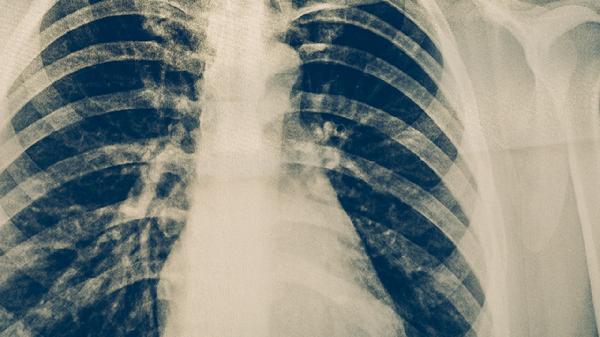

繼發(fā)性肺結(jié)核病變多局限于肺尖或鎖骨下區(qū),這與原發(fā)性肺結(jié)核的廣泛分布形成對比。由于人體免疫系統(tǒng)對結(jié)核分枝桿菌已有記憶性免疫反應(yīng),再次感染時病灶多局限在氧分壓較高的肺上葉。胸片可見斑片狀或結(jié)節(jié)狀陰影,邊界較清晰。這種情況需要規(guī)范使用異煙肼片、利福平膠囊、吡嗪酰胺片等抗結(jié)核藥物進行治療。

繼發(fā)性肺結(jié)核病灶易發(fā)生干酪樣壞死,這是其特征性病理改變。干酪樣物質(zhì)可經(jīng)支氣管排出形成空洞,空洞內(nèi)壁含有大量結(jié)核分枝桿菌,具有高度傳染性。胸部CT檢查可清楚顯示空洞壁的厚度和周圍浸潤情況。這種情況需要聯(lián)合使用乙胺丁醇片、鏈霉素注射液等藥物,必要時需考慮手術(shù)治療。